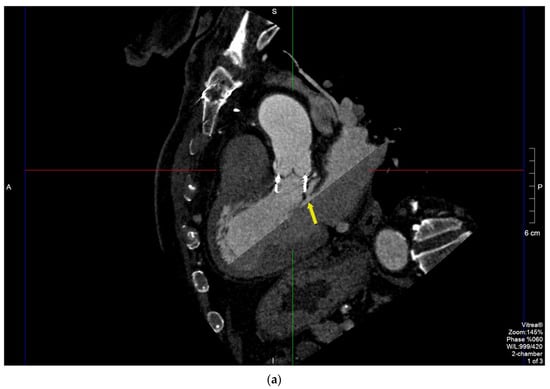

Male, 80 y/o, with a metabolic syndrome. He underwent thromboendarterectomy because of right internal carotid artery serrate stenosis. Due to bivasal critical coronary stenosis (anterior descending (DA) and left circumflex (LCx)) and severe degenerative aortic stenosis, he underwent coronary artery bypass graft (CABG: left internal mammary artery (LIMA-IVA)) and aortic bioprosthesis implantation (Intuity 25 mm) in 2019. Ten months after surgery, he started developing intermittent fever with serial hemocultures growing Enterococcus faecalis. TTE detected paravalvular regurgitation (PVR) with focal hyperechogenic thickening of the leaflets. Diagnosis of endocarditis was made, and antibiotic treatment was started (meropenem shifted to ampicillin and ceftriaxone according to the antibiogram). TEE showed a pulsatile perivalvular pseudoaneurysm in the mitroaortic intervalvular fibrosa (Supplementary Video S3). MDCT was performed a few hours later, confirming the presence of a pseudoaneurysm with the maximum axial size of 15 × 10 × 30 mm communicating with LVOT through a 5 mm window, and also detected a periaortic abscess in the anterolateral side of the vessel with longitudinal extension of 4 cm, which was only poorly detected by TEE (Figure 3a–c).

Figure 3.

MPR of the aortic annulus to better analyze the pseudoaneurysm (arrows) and its relations with contiguous structures. Long-axis (a,b) and short-axis views (c) of the peri-prosthesis abscess with discontinuous longitudinal extension for 4 cm communicating with LVOT through a 5 mm window.

In case 3, TTE detected paravalvular regurgitation (PVR), which raised the suspicion of endocarditis [2,11]. TEE detected a paravalvular pseudoaneurysm but failed to demonstrate the anterior abscess, and the overall quality of images was worse compared to MDCT due to acoustic shadowing. MDCT was indeed useful in confirming the presence and the size of the pseudoaneurysm by analyzing the mitroaortic intervalvular region with MPR [20,21].